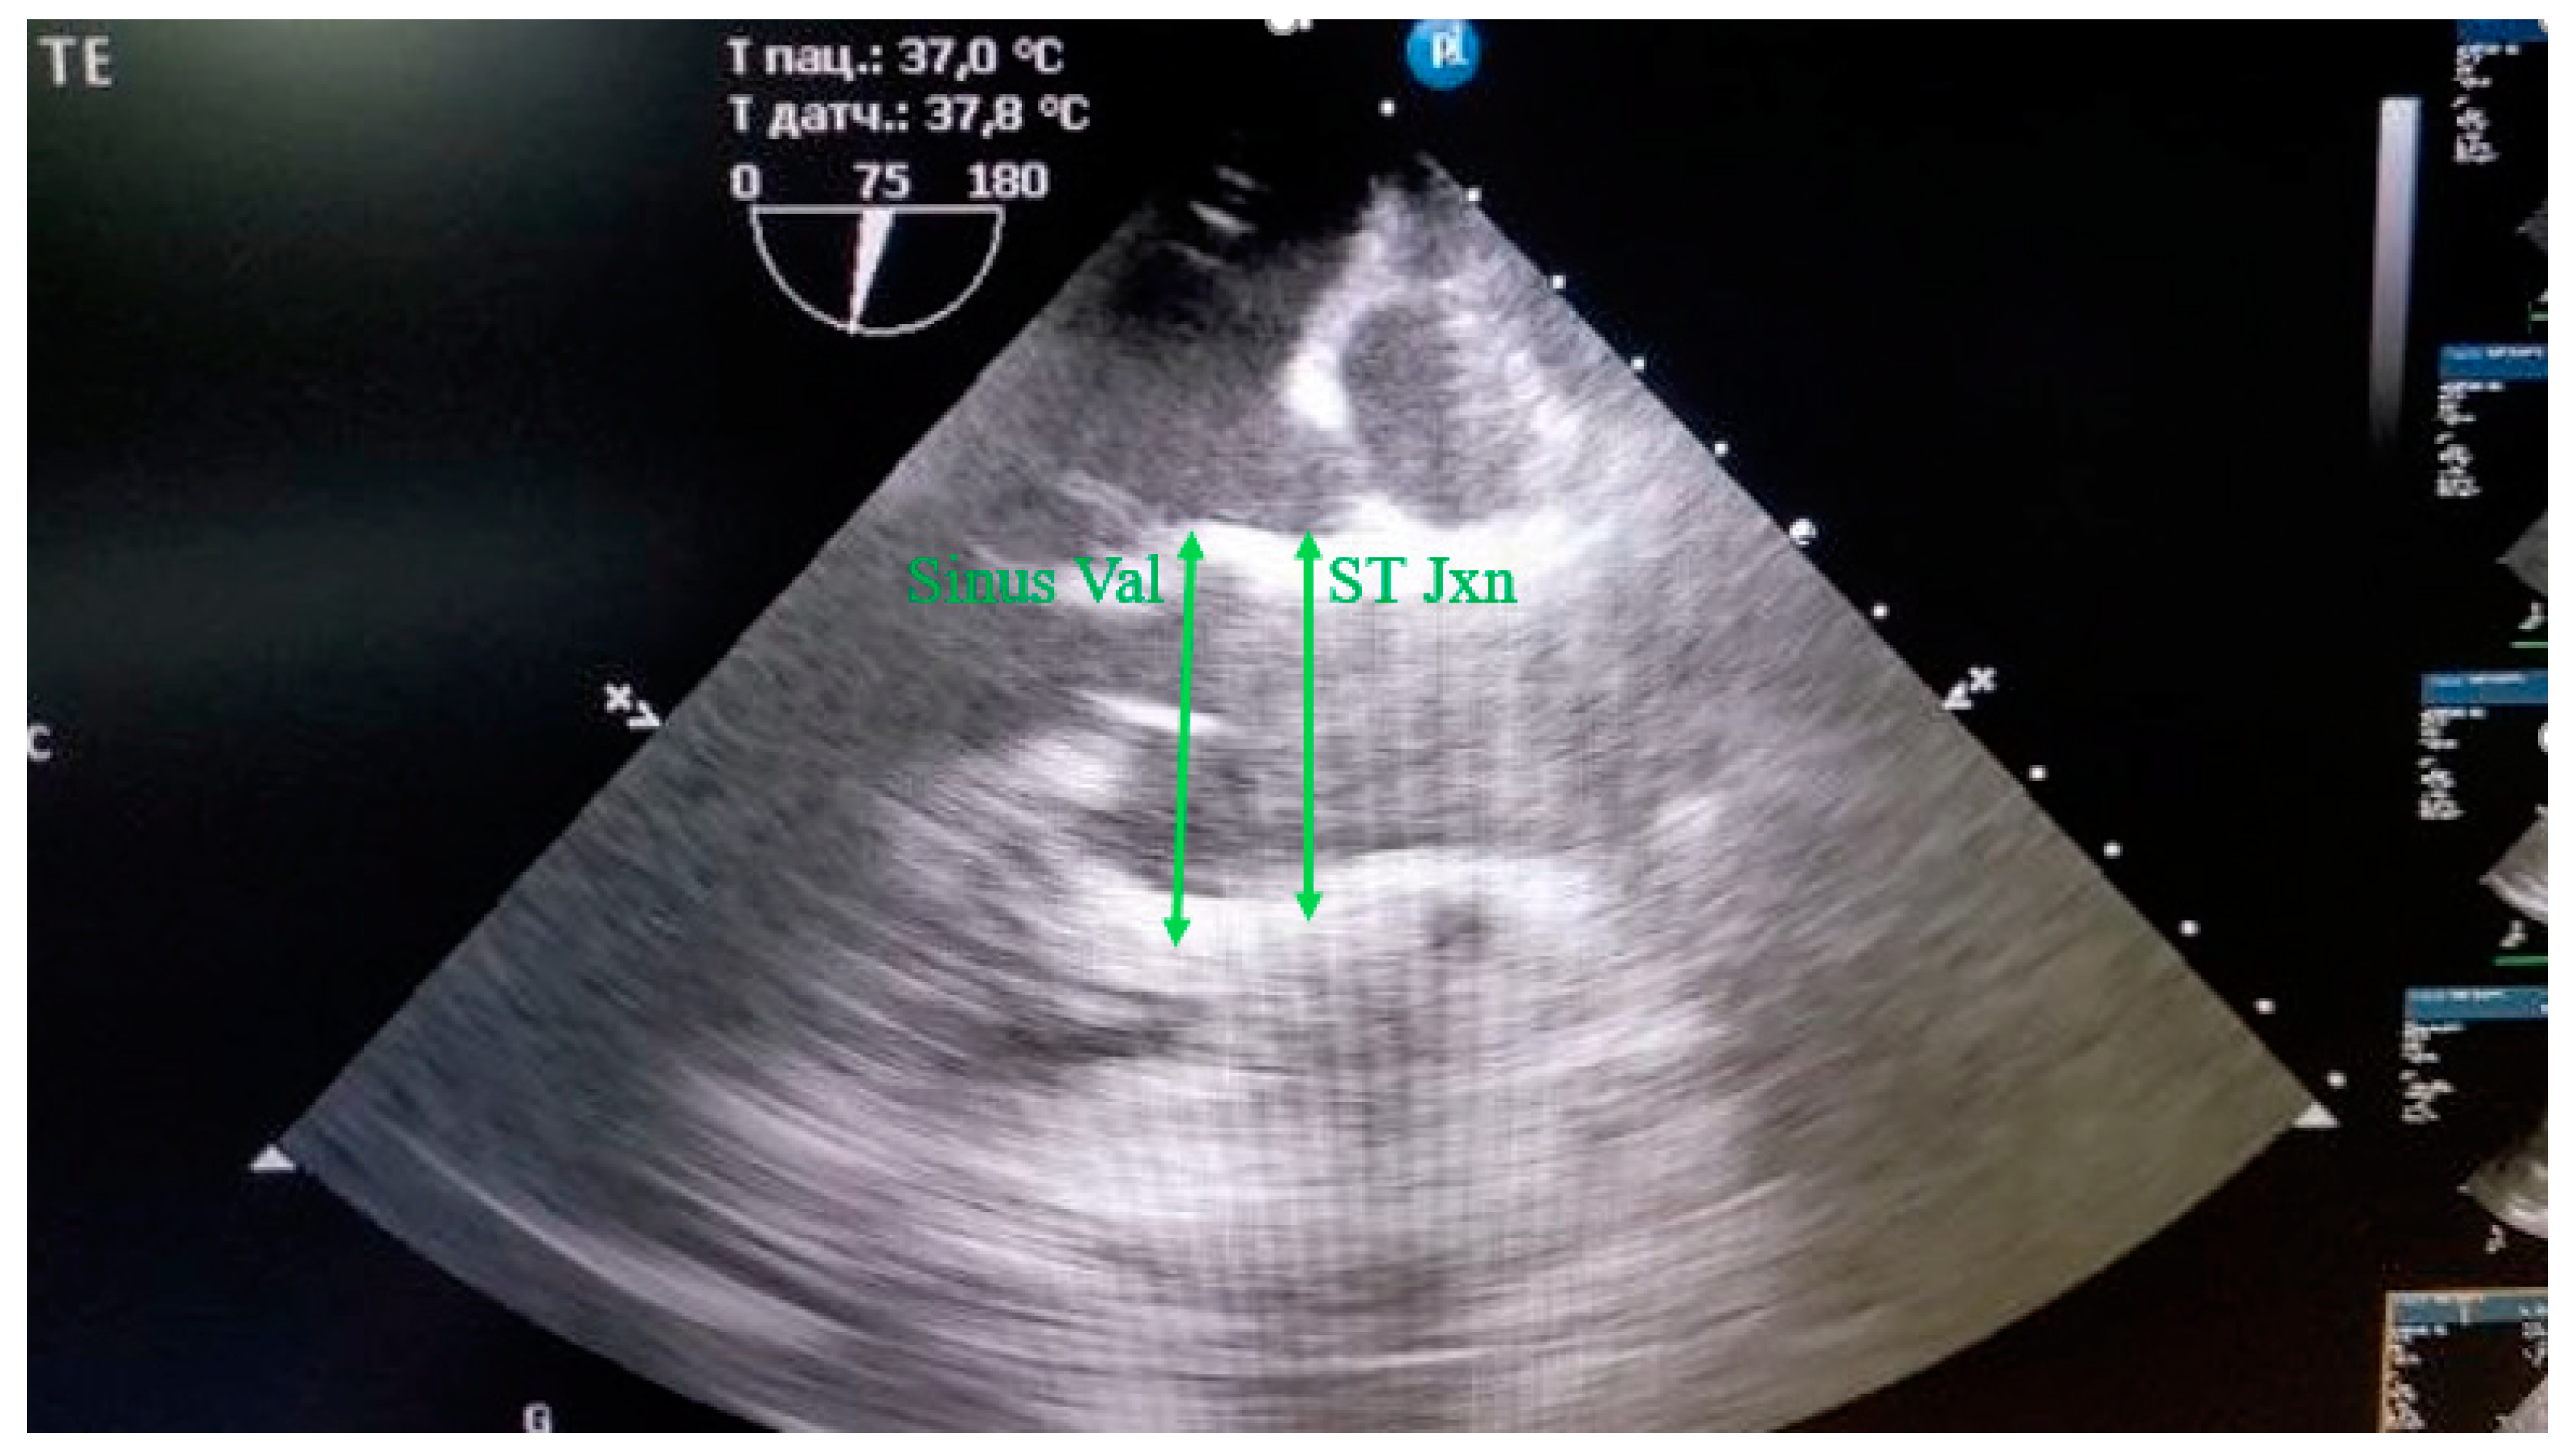

The sinus of Valsalva, the sinotubular junction was measured during diastole from the outer contour to the outer contour (Figure 3).

Figure 3. Measurement of the Sinus Valsalva (Sinus Val) and sinotubular junction (ST Jxn) in mini pigs from the outer contour to the outer contour during diastole.